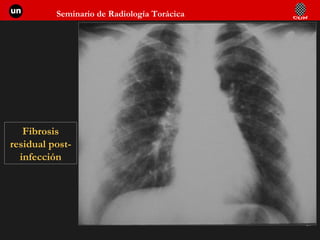

Fibrosis post-infección viral

Fibrosis residual post-infección